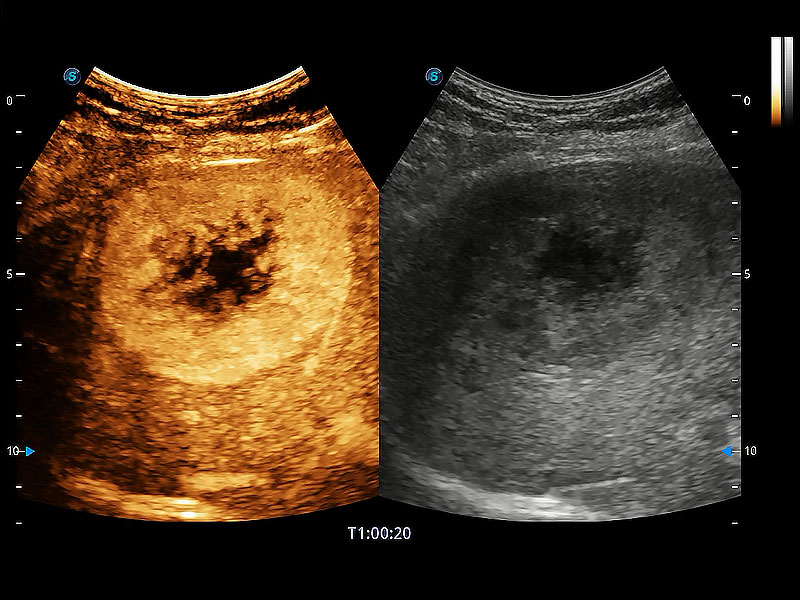

• 全面的造影成像

非线性融合造影成像充分利用谐波和基波信号,为难以观察的血流进行增强显像。可用于线阵、凸阵、微凸阵、相控阵探头。

(犬)肝脏